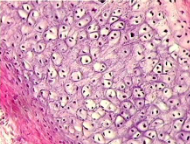

hyaline cartilage